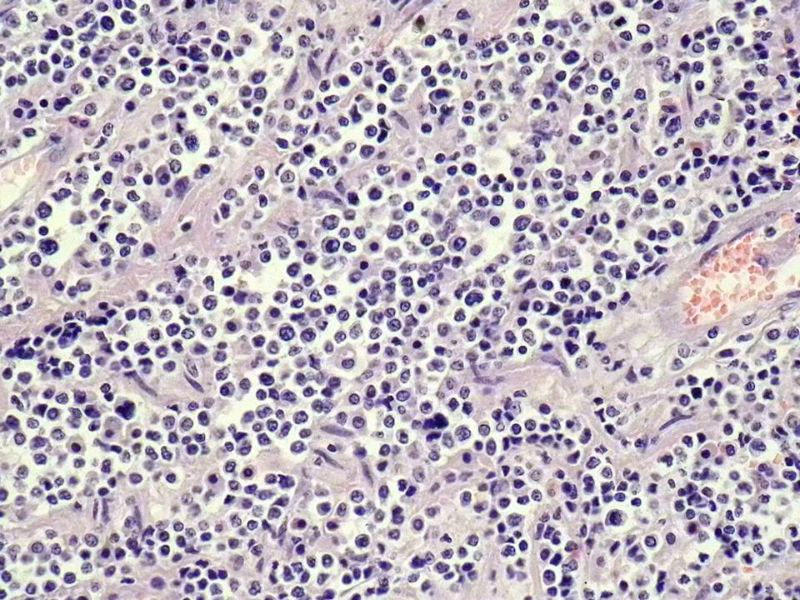

女,53岁,横结肠有9X6厘米大小溃疡,手术切除。

中老年人,溃疡很大,可见淋巴浆细胞样细胞弥漫浸润,散在大细胞,疑非霍奇颈淋巴瘤,倾向MALT伴浆样分化,不知是否破坏肌层?可否传肌层图?需IHC标记,鉴别淋巴瘤、腺癌及其它。

肉眼观仅是溃疡?有没有肠壁增厚、隆起?周围粘膜情况?肌层情况?有淋巴浆细胞样细胞、中心细胞,散在少量不成片的大细胞,不排除MALToma伴大细胞转化。

本例肉眼溃疡如溃疡性结肠炎,肠壁无明显增厚,表面辅以坏死,溃疡边缘稍隆起。镜下淋巴样细胞局限在粘膜层,肌层未见。谢谢!